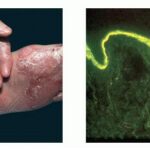

EBA is a chronic, sub-epidermal blistering disease associated with autoimmunity to the collagen (type VII collagen) within anchoring fibril structures that are located at the dermal-epidermal junction (DEJ). Although the precise etiology of EBA is unknown, most of the evidence suggests an autoimmune etiology. The immunoglobulin G (IgG) autoantibodies to type VII collagen are associated with a paucity of normal anchoring fibrils at the basement membrane zone (BMZ) separating the epidermis from the dermis and poor epidermal-dermal adherence. Although it is an acquired disease that usually begins in adulthood, it was placed in the category epidermolysis bullosa (EB) approximately 100 years ago because physicians were struck by how similar the clinical lesions of EBA were to those seen in children with hereditary dystrophic forms of EB. Direct immunofluorescence (DIF) of perilesional skin biopsies from EBA patients reveals IgG deposits at the DEJ.2 EBA antibodies bind to type VII collagen within anchoring fibrils

The classic presentation is of a noninflammatory bullous disease with an acral distribution that heals with scarring and milia formation. This presentation is reminiscent of porphyria cutanea tarda when it is mild and of the hereditary form of recessive dystrophic EB when it is severe . The classic form of EBA is thus a mechanobullous disease marked by skin fragility. These patients have erosions, tense blisters within noninflamed skin, and scars over trauma-prone surfaces such as the backs of the hands, knuckles, elbows, knees, sacral area, and toes . Some blisters may be hemorrhagic or develop scales, crusts, or erosions. The lesions heal with scarring and frequently with the formation of pearl-like milia cysts within the scarred areas . Although this presentation may be reminiscent of PCT, these patients do not have other hallmarks of PCT, such as hirsutism, a photodistribution of the eruption, or scleroderma-like changes, and their urinary porphyrins are within normal limits. A scarring alopecia and some degree of nail dystrophy may be seen.

Immunofluorescence

Patients with EBA have IgG deposits within the DEJ of their skin. This is best detected by DIF of a biopsy specimen obtained from a perilesional site (Fig. 58-6). IgG is the predominant immunoglobulin class, but deposits of complement, IgA, IgM, factor B, and properdin also may be detected. The DIF staining demonstrates an intense linear fluorescent band at the DEJ. Yaoita et al. have suggested that a positive DIF and IgG deposits within the sub-lamina densa zone are necessary criteria for the diagnosis of EBA.

The localization of the immune deposits within the DEJ of the skin of EBA patients by immunoelectron microscopy is the “gold standard” for the diagnosis. As demonstrated by Nieboer et al.22 and Yaoita et al.,2 patients with EBA have immune deposits within the sub-lamina densa zone of the cutaneous BMZ. This localization is clearly distinct from the deposits in BP, which are higher up in the hemidesmosome area or lamina lucida area of the basement membrane. It is also distinct from CP, which has antigenic targets confined to the lamina lucida .